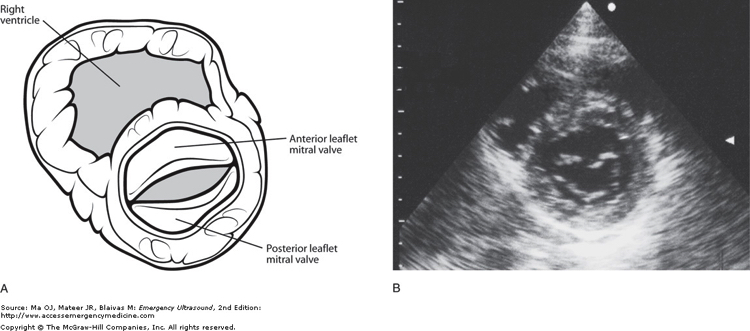

parasternal_short_mitral.jpeg